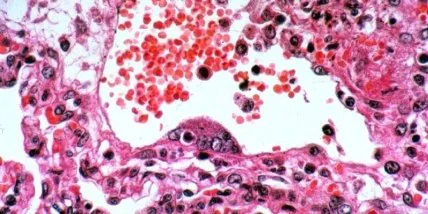

В мире опасаются новой пандемии, которую может спровоцировать вирус Nipah (Нипах) или NiV

Всемирная организация здравоохранения (ВОЗ) не исключает, что на фоне пандемии коронавируса COVID-19 может возникнуть и пандемия, вызванная так называемым вирусом Nipah (Нипах) или NiV.

Согласно двухгодичному отчету фонда, это одно из 10 инфекционных заболеваний из 16, определенных Всемирной организацией здравоохранения как наибольший риск для здоровья жителей планеты. Смертность от этого вируса составляет от 40 до 75%.

Инфекция у людей протекает в разных формах – от бессимптомной инфекции до острой респираторной инфекции (легкой или тяжелой) и до смертельного энцефалита.